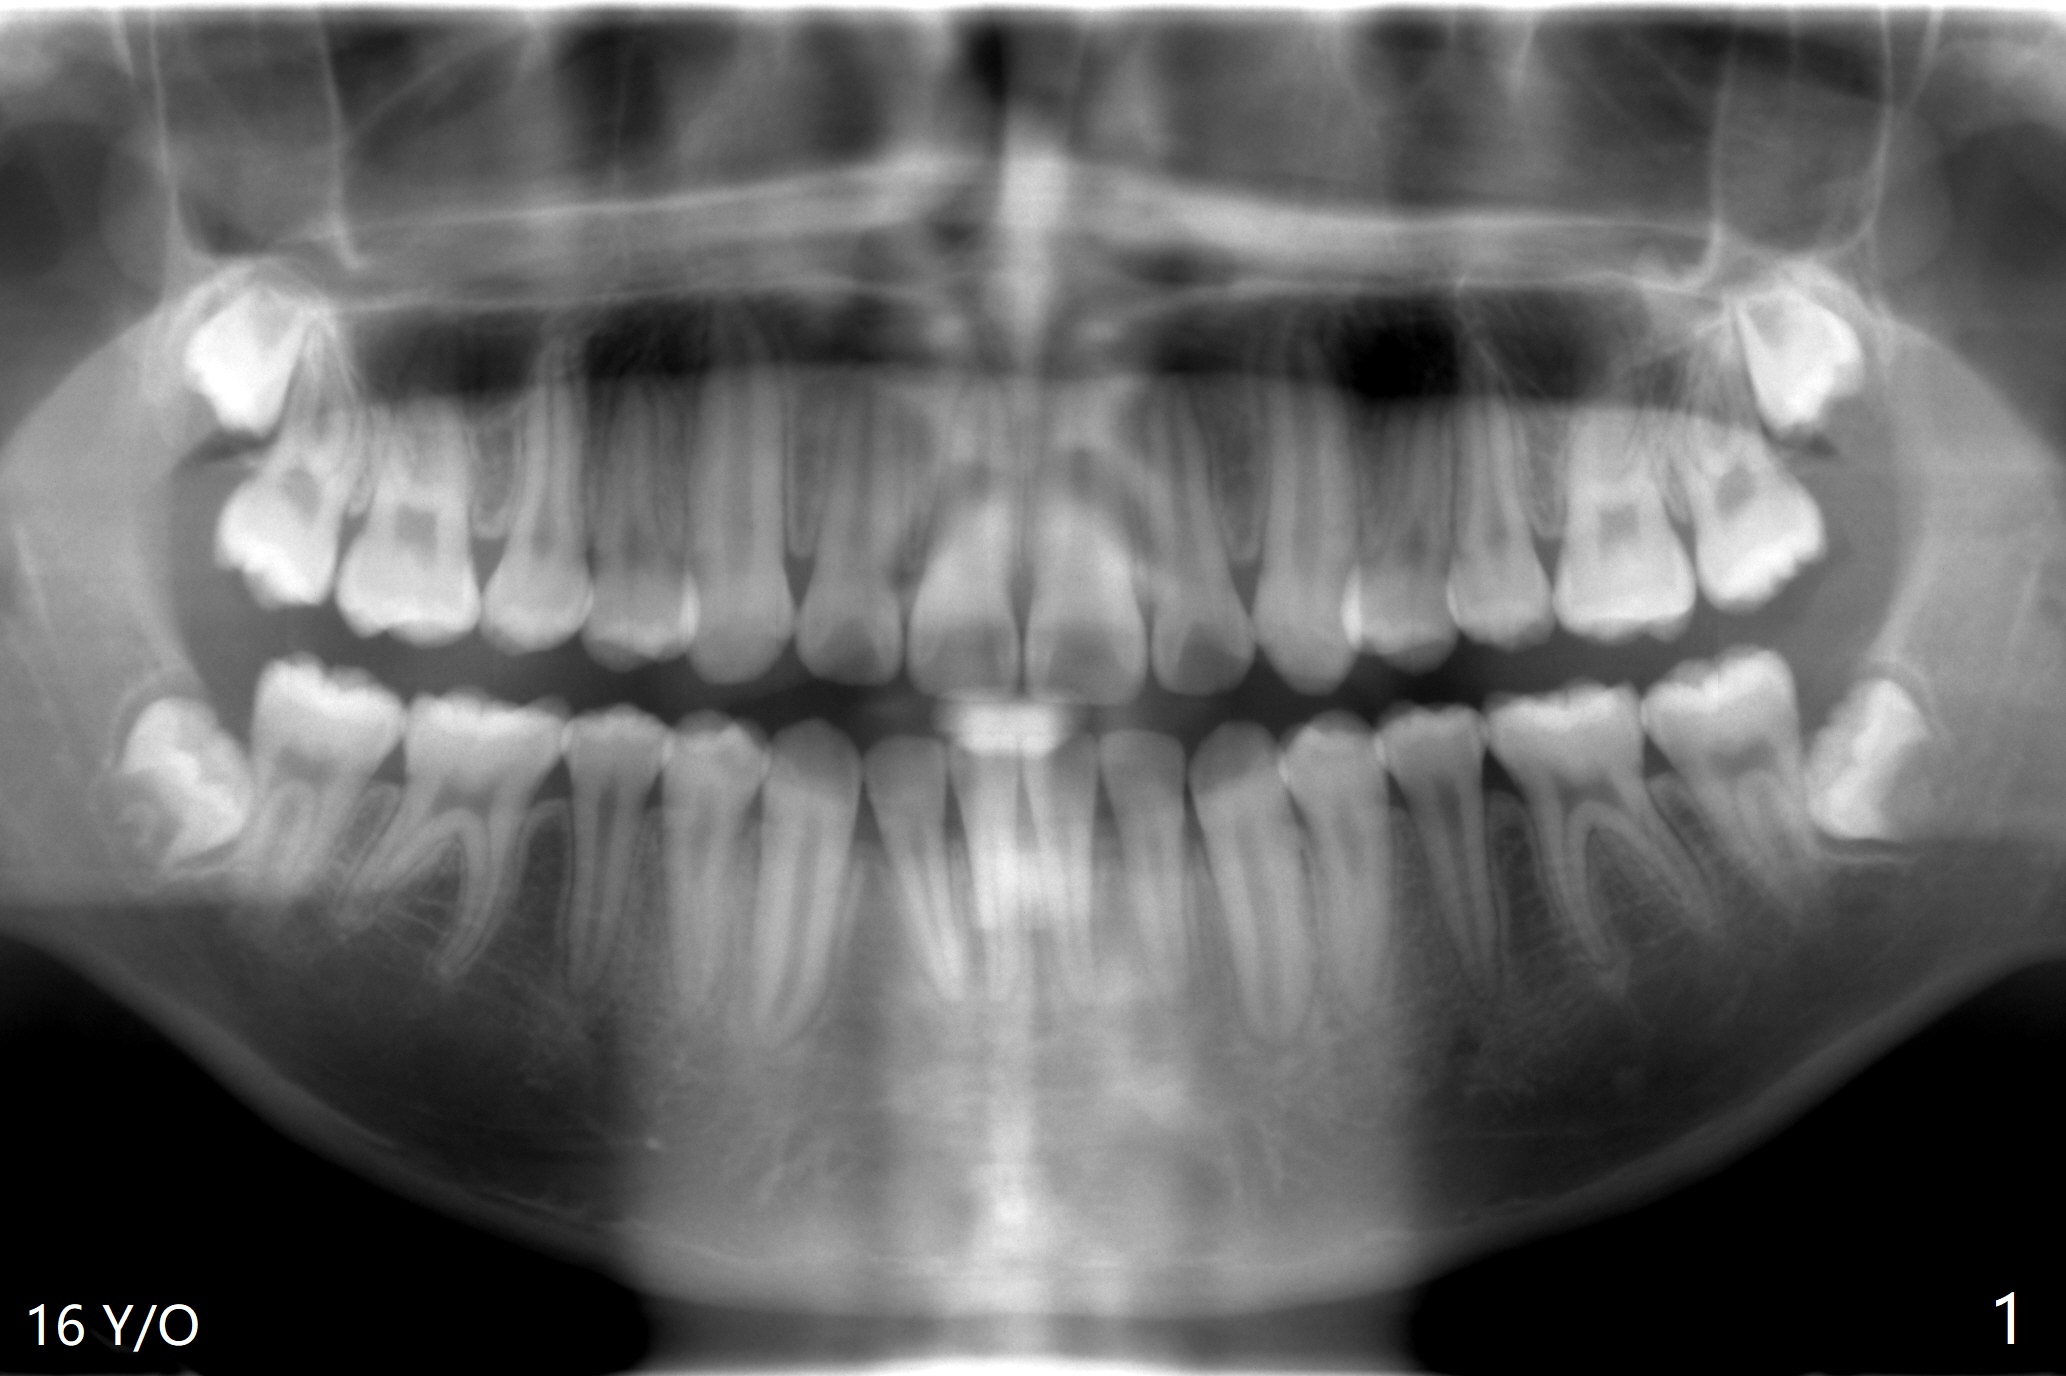

16岁男孩,上颌智齿在第二磨牙CEJ之上,太早拔除。下颌智齿牙根尚未形成,拔除困难,观察。